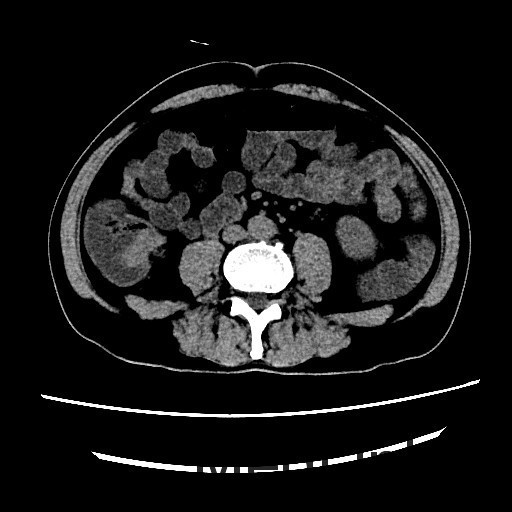

查体:腹平,腹软,肝区、双肾区无叩痛,腹部移动性浊音(-)。肠鸣音4次/分。双下肢无浮肿。 辅查:全腹螺旋CT平扫+增强:1、结肠肝区病变,考虑结肠癌,累及全层。2、直肠及乙状结肠病变,考虑炎症性病变。

讨论:本病例可以在CT冠状位看到结肠肝曲肠壁局限性增厚,属于浸润型结肠癌的表现,CT诊断结肠癌的时候,一般冠状位能够较好的显示结肠全貌,可以比较容易发现病灶,因此平常应先从冠状位发现胃肠道的病灶,再结合横断位诊断。作为影像医生除了报告癌肿,还需要注意一些临床关注的问题,比如癌肿与周围组织的关系,局部有无肿大淋巴结转移,其他脏器有无浸润或转移,在报告中提示这些情况,能够帮助临床选择合适的治疗方案。